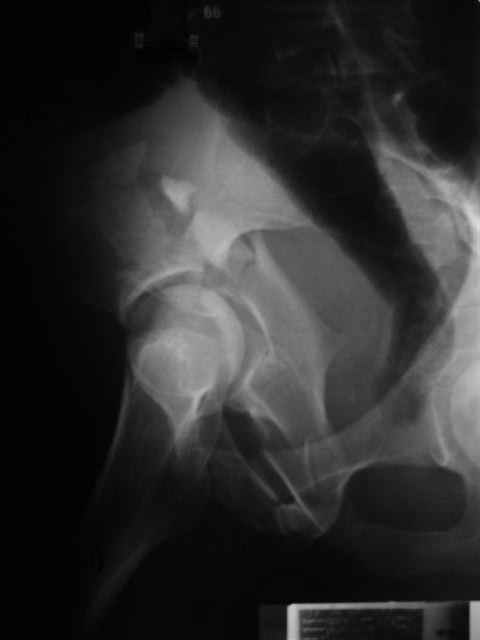

Уважаемые коллеги,43 летний мужчина, попав в автоаварию 13.10.2004, получил оскольчатый перелом обеих колонн левой вертлужной впадины.

На рентгенограммах - высокий двухколонный перелом вертлужной впадины с нарушением конгруэнтности, имеется обратная клиновидность суставной щели.

Причиной обращения к сообществу были возникшие непосредственно после операции сомнения и разочарования полученным качеством репозиции: а надо ли было трогать перелом вообще, репозиция передней колонны технически была очень сложна для меня, хотя реконструкции была в той же последовательности, что Д-р А.В.Рунков рекомендовал, в какой-то момент безуспешных манипуляций стал думать о *вторичной конгруэнтности*, которую не так давно обсуждали на

форуме и скелетном вытяжении. С репозицией и фиксацией задней колонны и отдельно задне-верхней стенки впадины проблем не возникло. Послеоп. Рг граммы в приложении. Если возникнут какие-либо дополнения или поправки - был бы признателен.